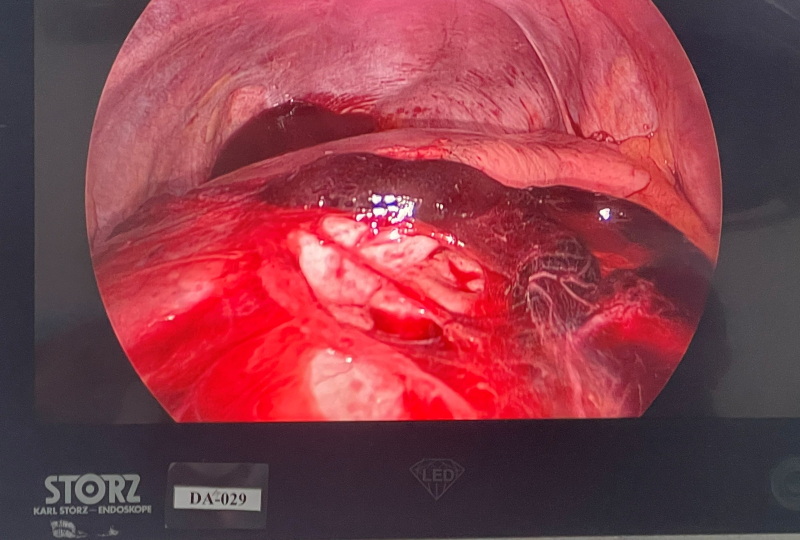

Hình ảnh tràn máu màng phổi trái.

Sau hơn 01 tiếng phẫu thuật, Bác sĩ CKI Hoàng Văn Quyết, Trưởng phòng Tổ chức cán bộ cùng Ekíp đã đã tiến hành Phẫu thuật nội soi lồng ngực cấp cứu, trong mổ hút được ~1000ml dịch máu lẫn máu cục trong khoang màng phổi, kiểm tra thấy có máu đang chảy ra từ dây chằng đỉnh phổi và từ thùy trên phổi trái do vỡ kén khí và đứt dây chằng. Bác sĩ đã tiến hành cầm máu điểm chảy máu, cắt và khâu lại kén khí vỡ, bơm rửa sạch và dẫn lưu khoang màng phổi. Hiện tại sau một ngày phẫu thuật, sức khỏe bệnh nhân đã ổn định.